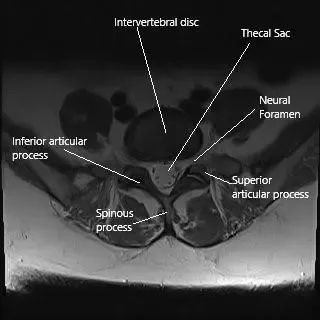

Sección axial de la columna lumbar a nivel L5.